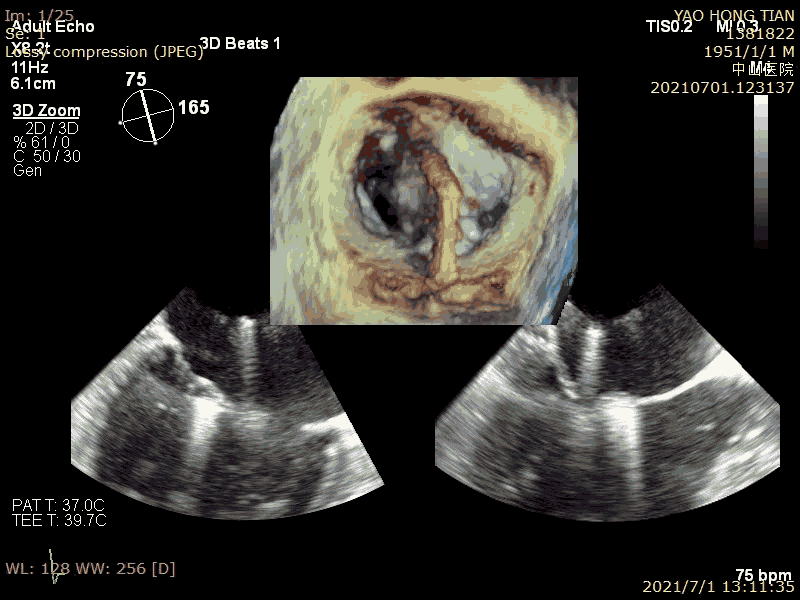

患者,男,70岁。术前超声诊断:左心室射血分数 LVEF 58%,左心室舒张末内径LVDD 52mm,左心房内径LAD 57mm,PASP 63mmHg,二尖瓣瓣尖错位导致重度二尖瓣反流,VC 6*13mm,反流面积19.8cm²(图1-2)。

术前大量反流(VC 6*13mm)

瓣尖错位导致A2P2大量反流